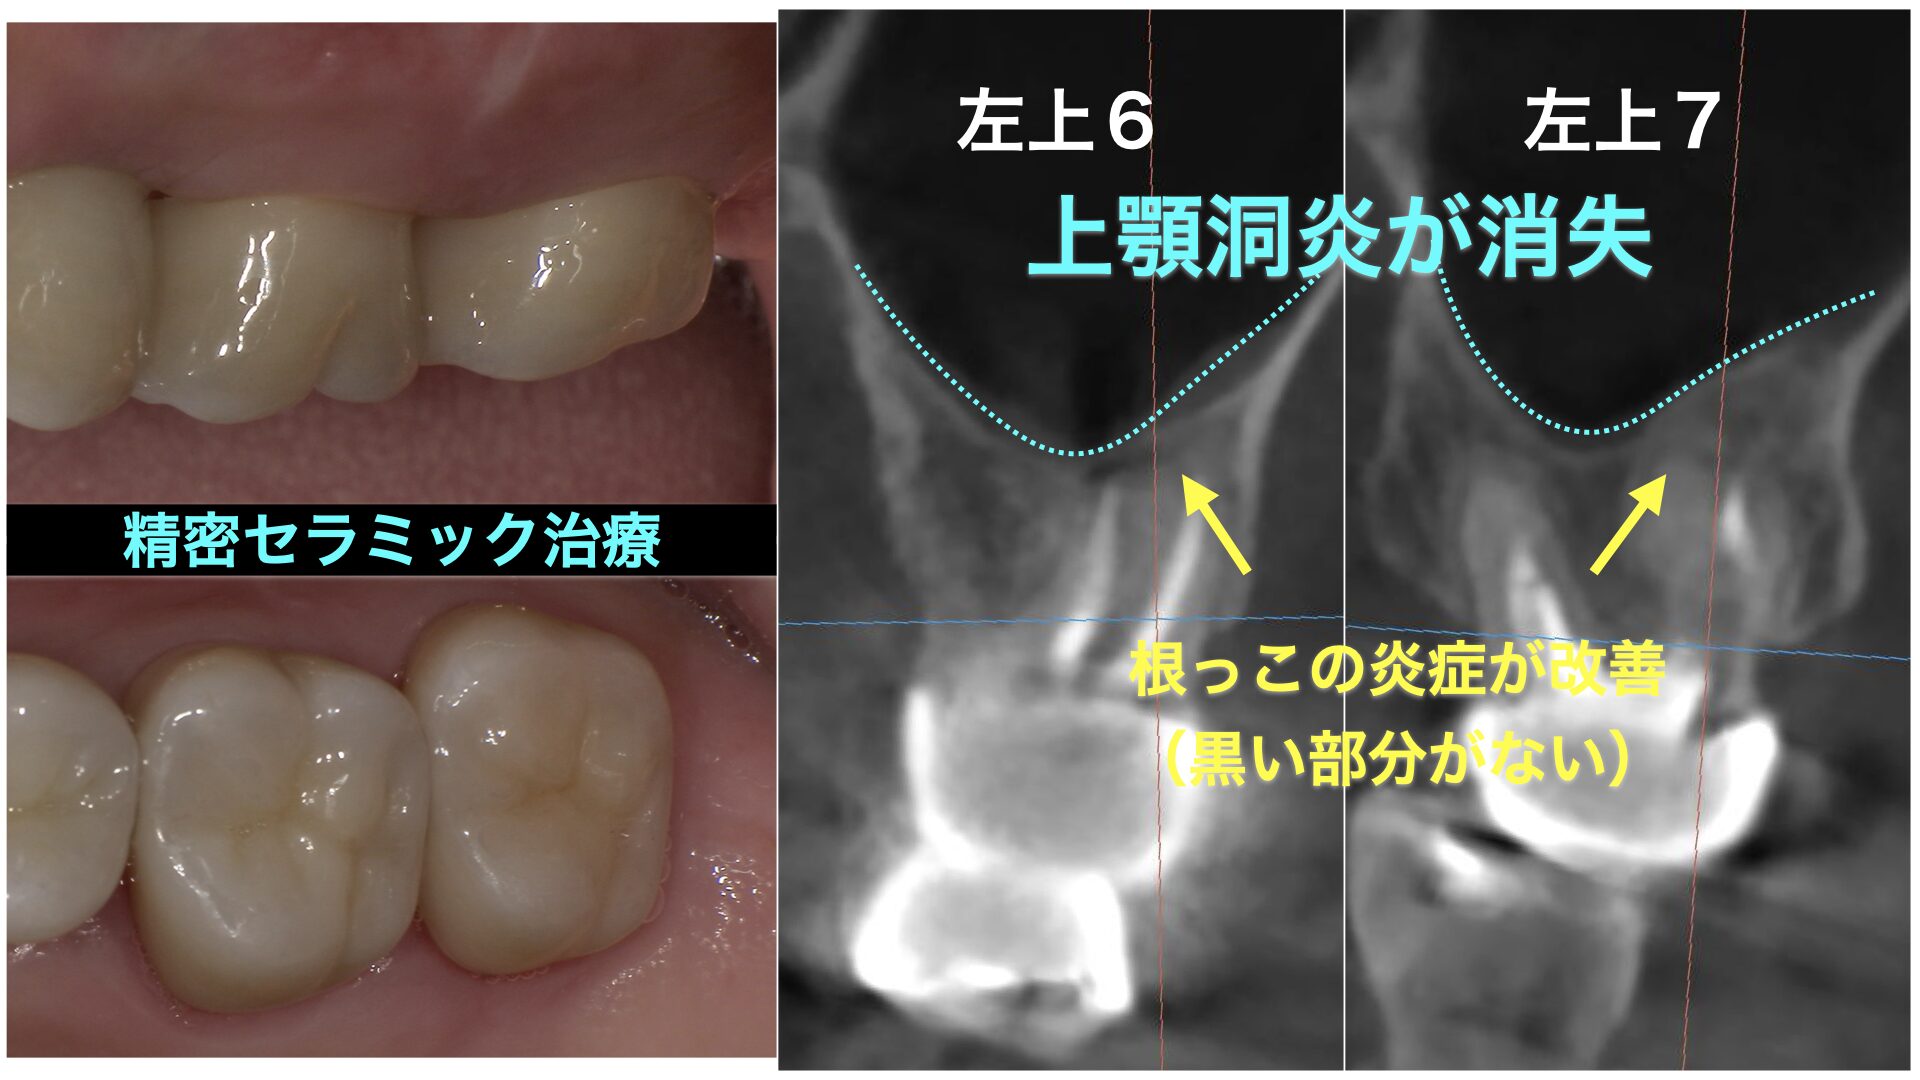

CASE 症例紹介

当院では、歯周病治療やインプラント治療、セラミック治療、審美治療など、様々な治療オプションを用いて、お口の中全体を管理しています。

院長が施術してきた症例をご確認のうえ、お気軽にご相談・ご来院ください。